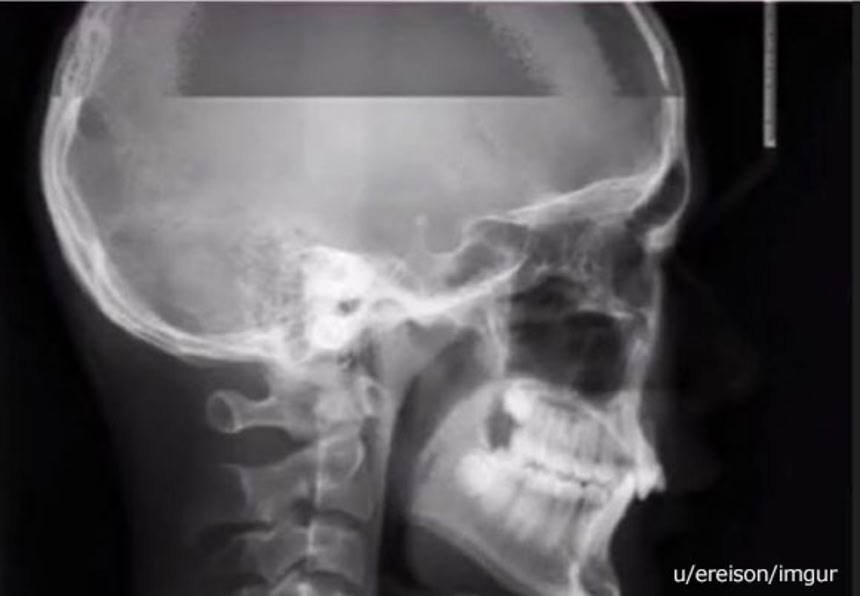

続きを読むX線を目的の物質に照射し、透過したX線を検出器で可視化することで…